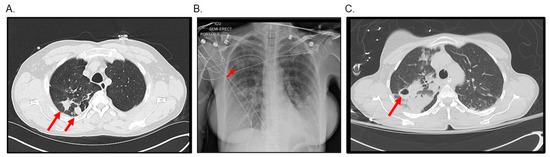

- New or worsening radiologic findings suggestive of nodular, cavitary opacities on chest X-ray or bronchiectasis with nodules on computed tomography (CT).